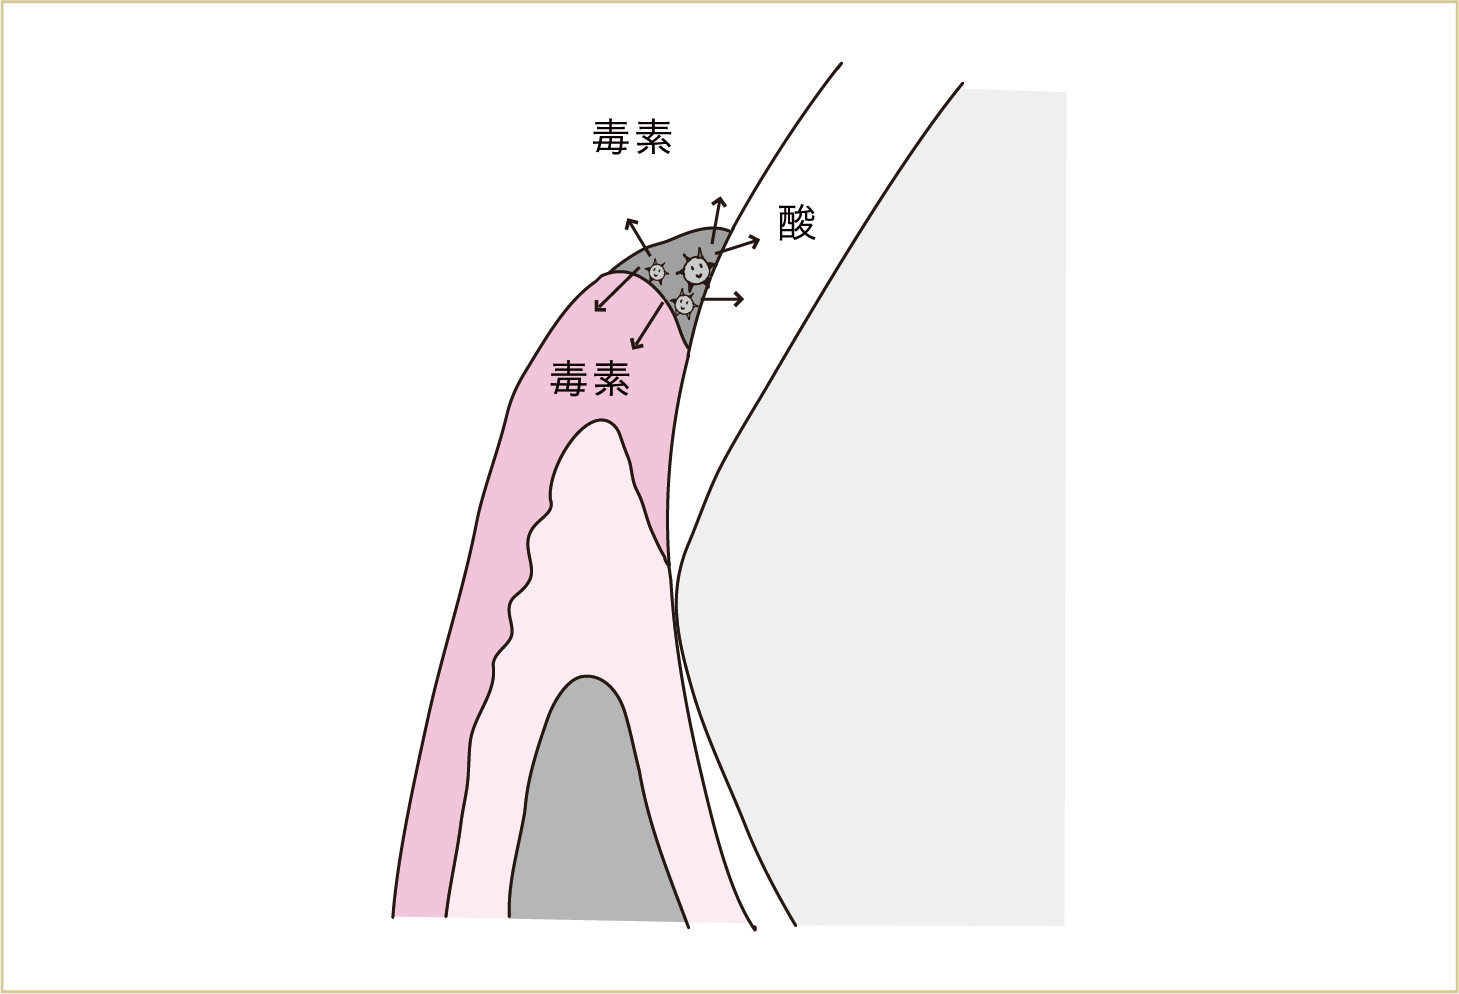

細菌も私たちと同じように生きています。生きているということは、私たちが出す汗や老廃物のように、細菌たちもいろいろな代謝産物を出したりするということです。これが口の中に出ていって、歯肉や歯に触れたりします。この細菌たちの汗であったり、老廃物であったりするものが、歯肉にとっては毒の役割をします。

細菌は、酸や毒素など、いろいろな代謝産物を周囲にまきちらす。毒素は歯肉に対して毒の働きをし、口臭の原因にもなる。また酸で歯が溶けて虫歯になる。